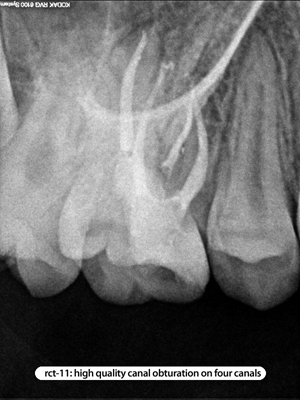

Root Canal Cases